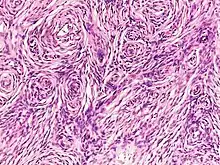

| Neurofibroma of the skin in a person with neurofibromatosis type I | |

Neurofibromas arise from nonmyelinating-type Schwann cells that exhibit biallelic inactivation of the NF1 gene that codes for the protein neurofibromin.[2] This protein is responsible for regulating the RAS-mediated cell growth signaling pathway. In contrast to schwannomas, another type of tumor arising from Schwann cells, neurofibromas incorporate many additional types of cells and structural elements in addition to Schwann cells, making it difficult to identify and understand all the mechanisms through which they originate and develop.[3]

Schwann cells

There are two kinds of Schwann cells, myelinating and nonmyelinating. While myelinating Schwann cells cover large diameter (>1 micrometer) peripheral nervous system (PNS) axons with myelin, nonmyelinating Schwann cells encapsulate small diameter PNS axons with their cytoplasmic processes. Nonmyelinating Schwann cells are the neoplastic element in neurofibromas. This conglomeration of nonmyelinating Schwann cells and axons is called a Remak bundle.

While nonmyelinating Schwann cells are the origin of neurofibromas, the mutations that make them susceptible to this transformation occur in Schwann cell precursors during early nerve development. Mutated nonmyelinating Schwann cells do not form normal Remak bundles. Instead, they fail to properly surround and segregate target axons. It is unknown at this time why, if both types of Schwann cells exhibit bilallelic inactivation of the NF1 gene, only the nonmyelinating variety give rise to neurofibromas.[12]